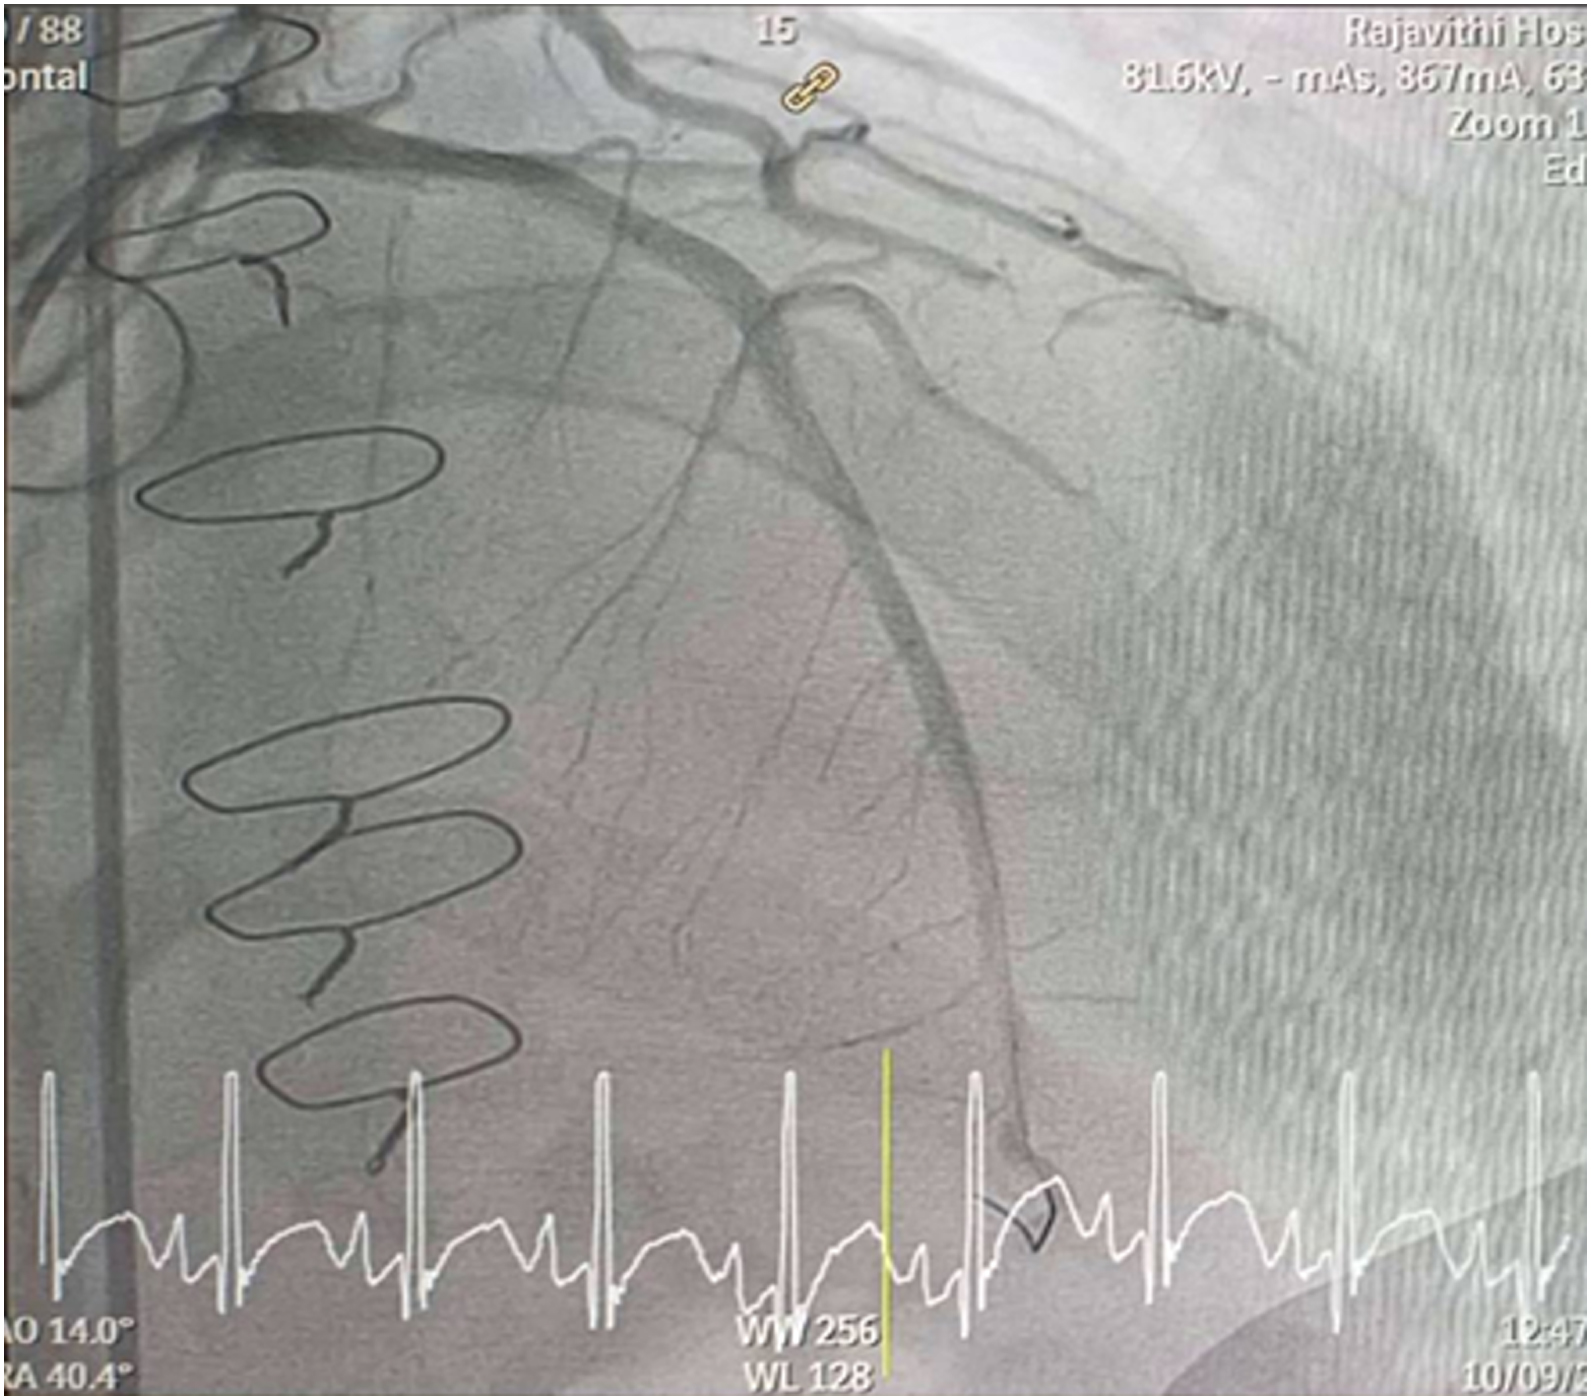

Inserted Sion wire and thrombuster to LAD revealed multiple red clots.SC balloon 2.0 x 15 mm, then 2.5 x 15 mm, was inflated at mLAD up to 12 atm. IVUS insertion to LAD revealed vessels¡¯ size LM 5-5.5 mm, pLAD 4-4.5 mm, mLAD 3-3.5 mm with intraluminal thrombus, dLAD 2.75-3 mm. Multiple inflations were done at mLAD with SC balloon 2.5 x 15 mm. After multiple SC balloon inflations, the CAG revealed slow flow phenomenon. Then, the operator performed thrombus aspiration, multiple SC balloon 2.0 x 15 mm inflation and gave IC integrillin 3.4 ml. The final angiogram was acceptable result. The anticoagulant was given after CAG. Chest pain was subsided and hemodynamic parameters remained stable. EKG recorded after angiography showed resolution of ST elevation at V1-3. Later, the patient was discharged with warfarin. The Aortomitral intervalvular fibrosa repair surgery was planned due to embolic complication.